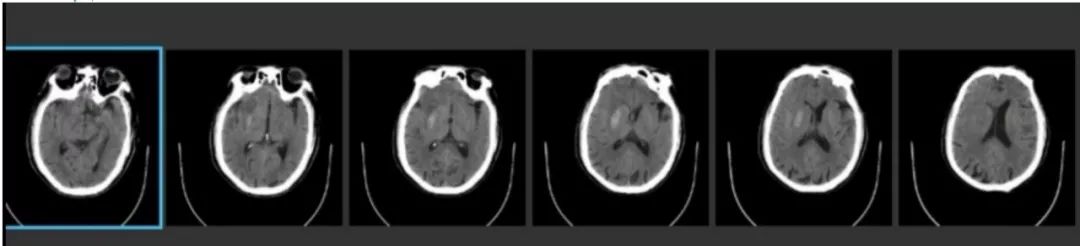

术前CT

ASPECTS评分 8分

术后即刻CT

术后24h CT